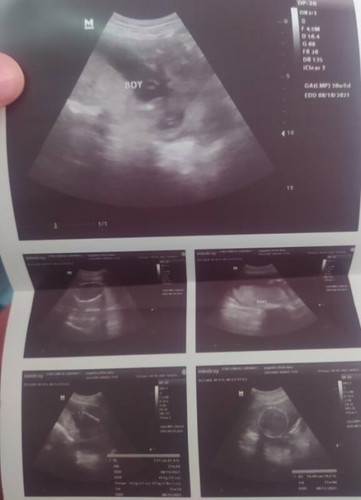

TEAM AUGUST! ❤️

Hello team august! Nakapag pa ultrasound na ba kayo? Hehe, ako nito lang nag pa utz and I'm having a baby boy! Obvious na obvious sa pic, kitang kita pututoy ni baby 😂😂 We're expecting a girl pero still blessed for having a baby boy! May kuya na agad hehe. 🥰❤️ #1stimemom #firstbaby

ako nga boy din di mkapaniwala tinanong kopa sonologist kung 100% sure naba yun😁😁 sabi nya" sure yun nakita ko boy siya" hahah pagtingin ko may lawit nga 😂😂😂

Nakakatawa po talaga pag nakita agad sa ultrasound yung lawit. Boy din po samin, ang aga pinakita ng putotoy nya. 😂